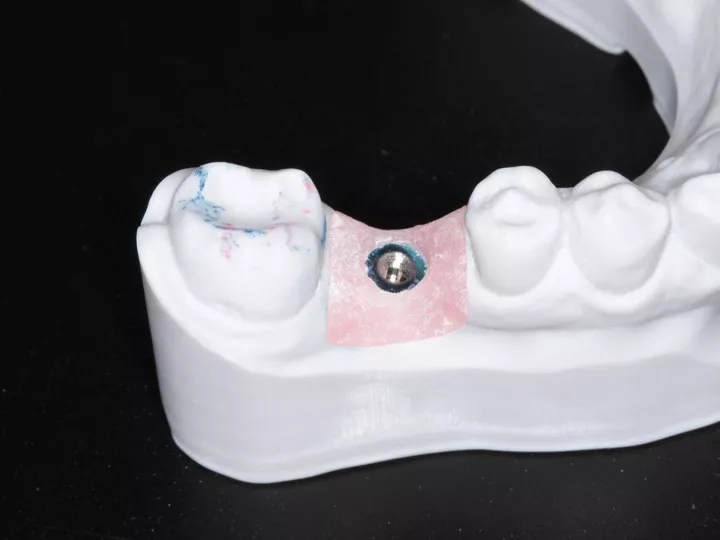

13. Maître modèle.

14a. 14b. 14c. Une empreinte optique a été réalisée (à l'aide du scan body TL). Le fichier a été envoyé au centre d'usinage Simeda® et la restauration finale (Pilier CAD/CAM et couronne en zircone) a été livrée.